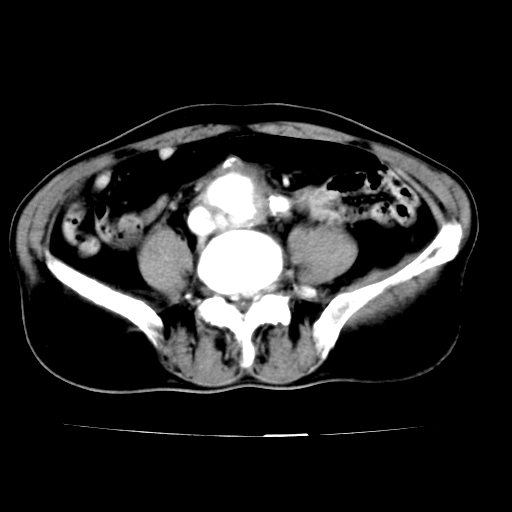

标题: V0243:右髂总动脉瘤附壁血栓形成?破裂?动静脉瘘? [打印本页]

标题: V0243:右髂总动脉瘤附壁血栓形成?破裂?动静脉瘘?

男,75岁,腹痛月余,彩超发现脐周腹主动脉异常回声。临床诊断:腹主动脉瘤。

ct诊断:右骼总动脉囊性动脉瘤并瘤内附壁血栓形成,与下腔静脉之间形成动静脉瘘。

请问各位老师:能排除动脉瘤破裂的可能吗?

各位老师注意到下腔静脉的充盈缺损了吗?注意到动静脉漏了吗?

当时是扫描的标准动脉期,可是下腔静脉与腹主动脉同步强化且幅度一致。所以我想动静脉瘘是存在的。